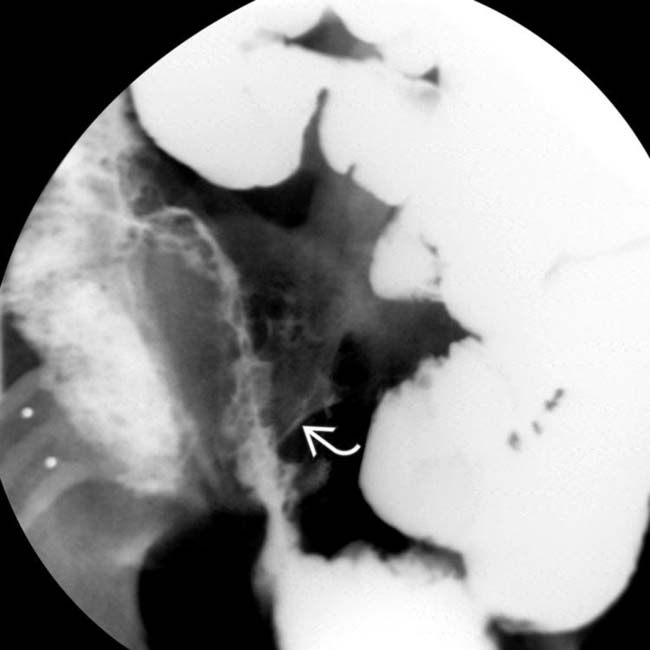

Crohn's disease, Xray Stock Image M130/0880 Science Photo Library